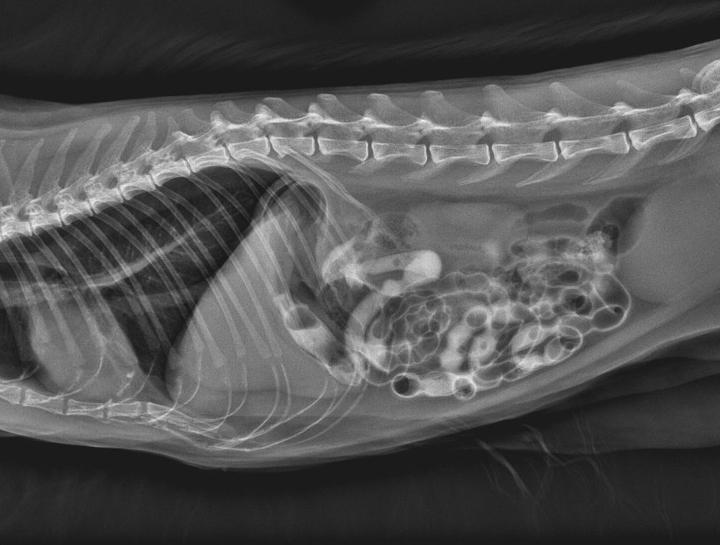

Diagnostic imaging can be an alternative to invasive exploratory surgery. It allows us to examine pets internal organs and body systems to better diagnose their conditions. There are different types of diagnostic imaging and the type your pet needs will depend on their symptoms and the affected area of the body.

Pet Digital Radiology

Digital x-rays assist in diagnosing illness & injury.